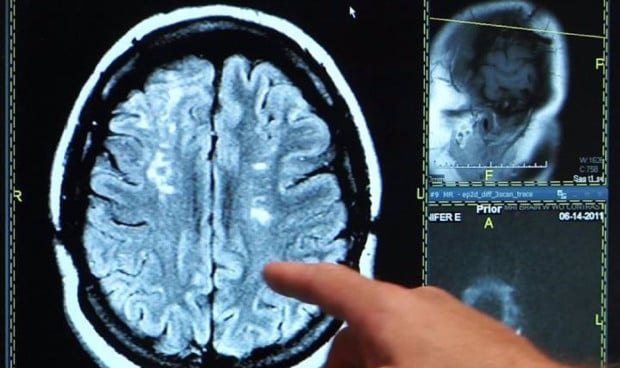

El dinero no siempre es sinónimo de felicidad, pero las personas con altos ingresos sí consiguen tener un menor riesgo de mortalidad posterior a un accidente cerebrovascular. Esta conclusión es fruto de una nueva investigación realizada por la Universidad de Gotemburgo (Suecia), después de basarse en un registro que analizó datos de 6.901 pacientes con accidente cerebrovascular en Gotemburgo entre noviembre de 2014 y diciembre de 2019.

Los investigadores analizaron el impacto de los factores SDoH en el riesgo de mortalidad posterior al accidente cerebrovascular, centrándose en cuatro factores SDoH: zona de residencia, país de nacimiento, educación e ingresos.